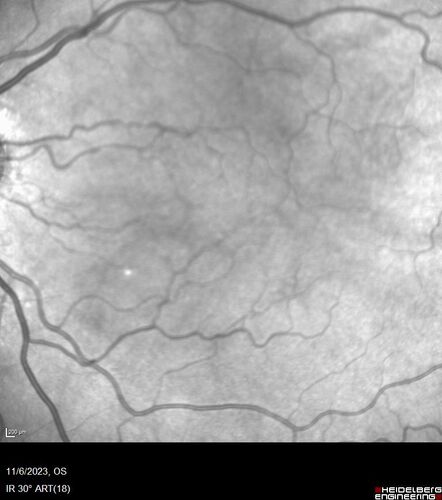

Albinism and Renal failure - Possible Hermansky-Pudlak Syndrome

65 year old female with foveal hypoplasia and renal failure since age 18. VA 20/40 OD, 20/63 OS